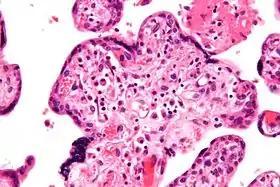

![]() صورة مجهرية لالتهاب الزُغابات مجهول السَبب، الصبغة المُستعملة هي صبغة الهيماتوكسيلين والإيوسين صورة مجهرية لالتهاب الزُغابات مجهول السَبب، الصبغة المُستعملة هي صبغة الهيماتوكسيلين والإيوسين | |

حَسب علم أمراض الانسجة فَإنَّ التهاب الزُغابات مجهول السَبب يتميز بارتشاح لمفاوي مجهول السَبب، وَيتميز بعدم تواجد الخلايا البلازمية، حيثُ أنَّ وجود الخلايا البلازمية أثناء الالتهاب يُدل على أنَّ سَبب الالتهاب هوَ العدوى، مِثل العدوى بالفيروس مضخم الخلايا.

التهاب الزغابات مجهول السبب (تكبير مُرتفع)